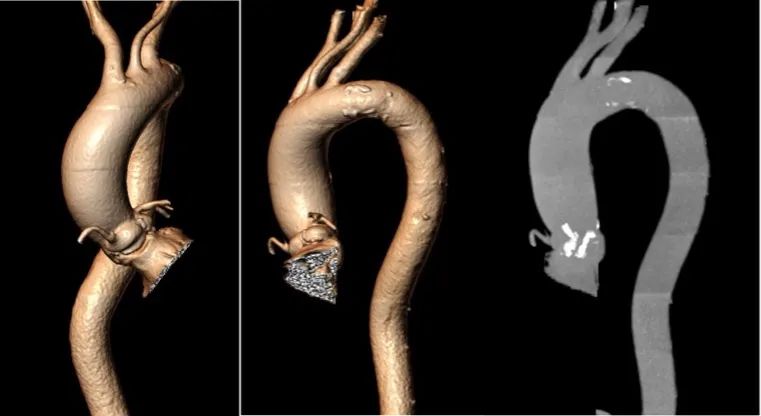

主动脉弓: